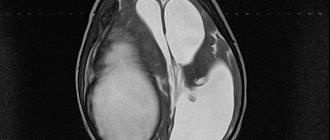

- magnetic resonance imaging of the brain;

- MRI of cerebral vessels;